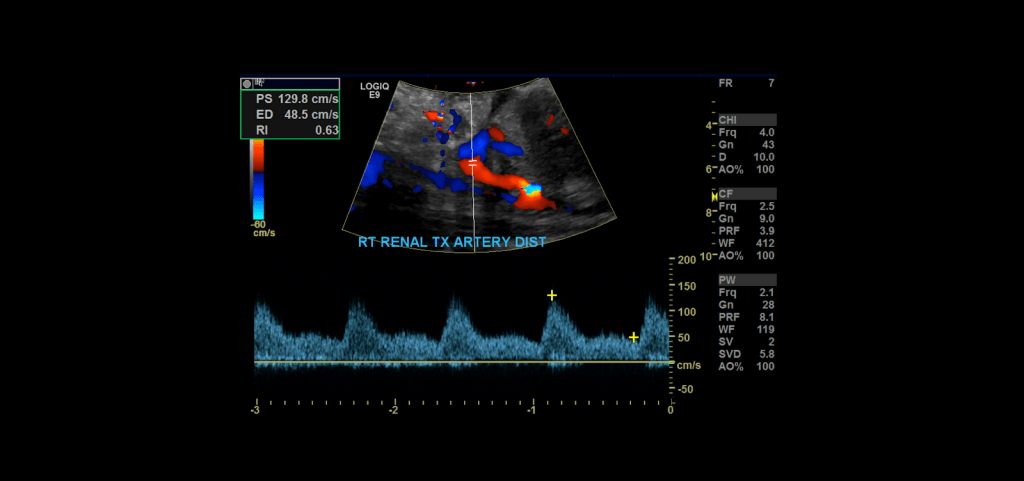

Proceed to doppler the transplant main renal artery and vein. Given the tortuosity sometimes seen in the donor arteries, measuring velocities with angle correction can be tricky. My rule of thumb is that if the artery is perpendicular to the transducer face I don’t use angle correction. If it is parallel to the transducer face I do use angle correction.

Measure the peak systolic and end diastolic velocity. Resistive Index is normally between 0.50 and 0.70. The waveform should be a low resistance waveform with forward flow throughout the cardiac cycle. Take Doppler samples at the anastomosis/proximal section (pay close attention here look for aliasing to detect anastomotic stenosis), the mid and distal portions as well. If there’s any aliasing along the vessel take spectral Doppler samples there too.